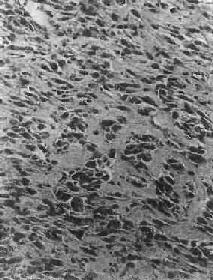

镜下,骨肉瘤由明显间变的梭形或多边形肉瘤细胞组成,细胞大小不等,核形奇异,大而深染,核仁明显,易见病理性核分裂像。肿瘤细胞直接形成肿瘤性类骨组织或骨组织,是诊断骨肉瘤的最重要的组织学依据。所形成的类骨组织或骨组织在不同肿瘤或同一肿瘤的不同部位多少不等。往往可看到肿瘤性骨质发生过程中各阶段的形态,最早期在恶性肿瘤细胞间出现均质红染的胶原样物质,其后红染物质逐渐增多,将肿瘤细胞分隔疏远,构成小梁或片状的肿瘤性类骨组织(图17-8)。类骨组织可伴钙盐沉着,其内的肿瘤细胞固缩变小,形成肿瘤性骨质。骨肉瘤内也可出现肿瘤性软骨(图17-9)。

图17-8 骨肉瘤

多形性肉瘤细胞直接形成肿瘤性骨样组织